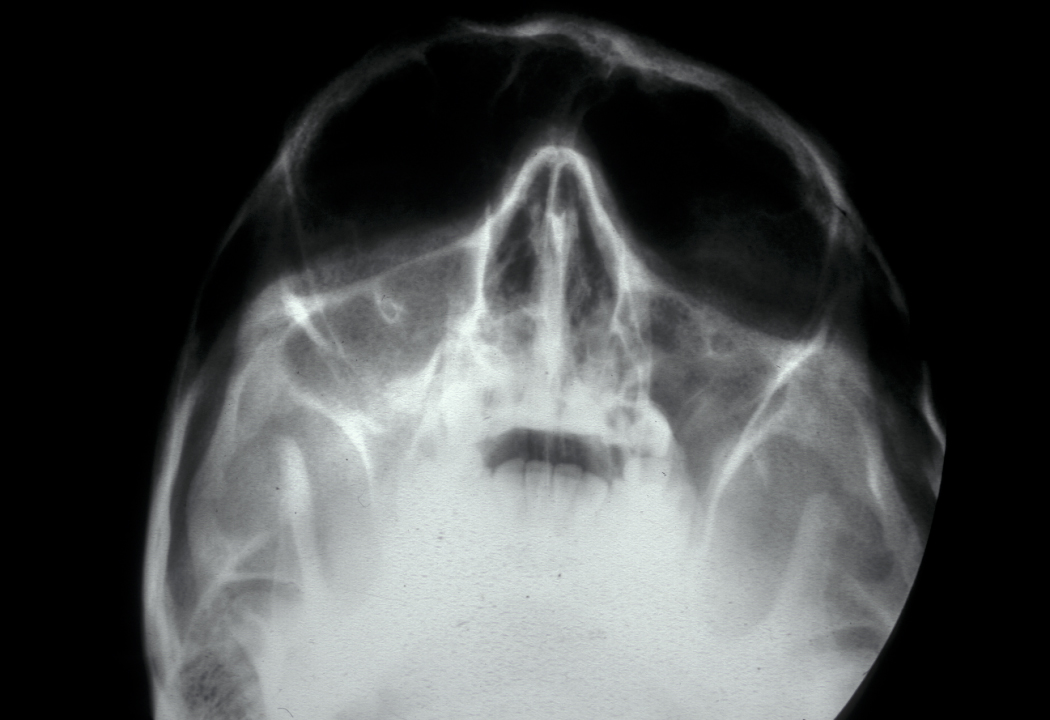

Imaging may be difficult because the radiographic findings lag behind the clinical stage. The first radiographic sign (see Figure 3) may be radiopacity which represents the sequestrum that has lost its non-mineralised components. Bone scans (PET scans) show osteomyelitis as areas of increased bone turnover (‘hot spots’).

Figure 3: Chronic osteomyelitis of the right mandible. Note the loss of the right condyle (part of the mandible forming the jaw joint) and the diffuse radiopacity of the right body of the mandible.